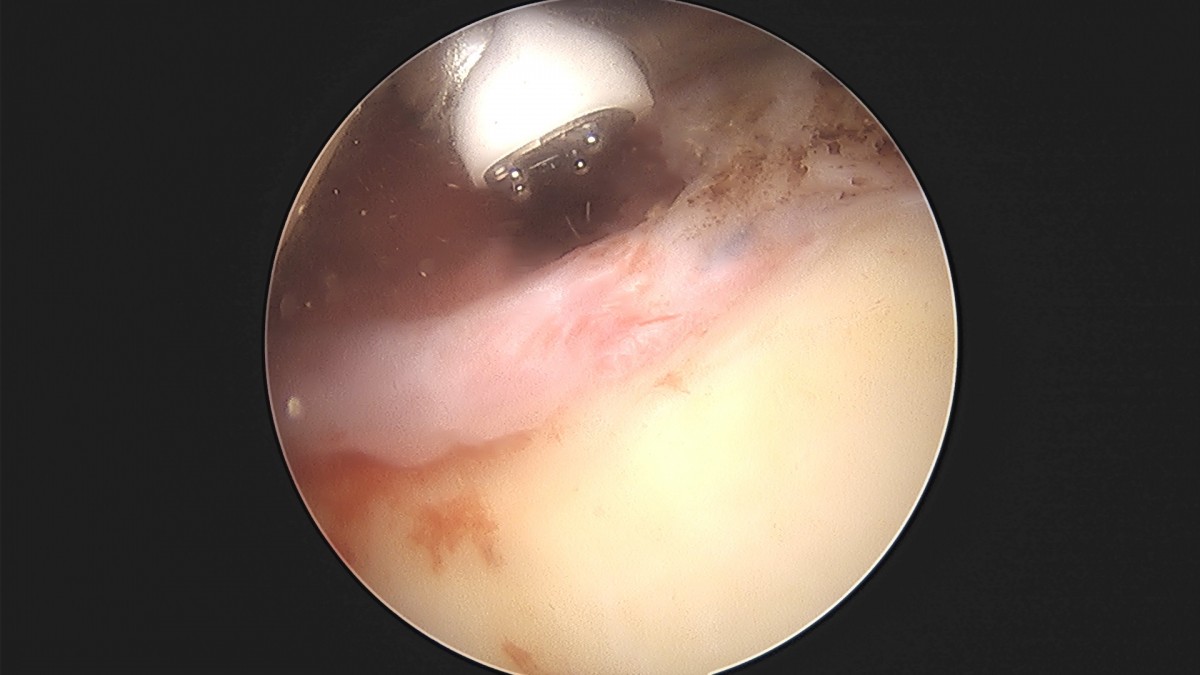

이재상원장님 어깨 견봉하 감압술 및 관절낭 이완술 박창O 환자

dae765e4d9ac96aee867c9d6292d8784_1758004611_6449.jpg